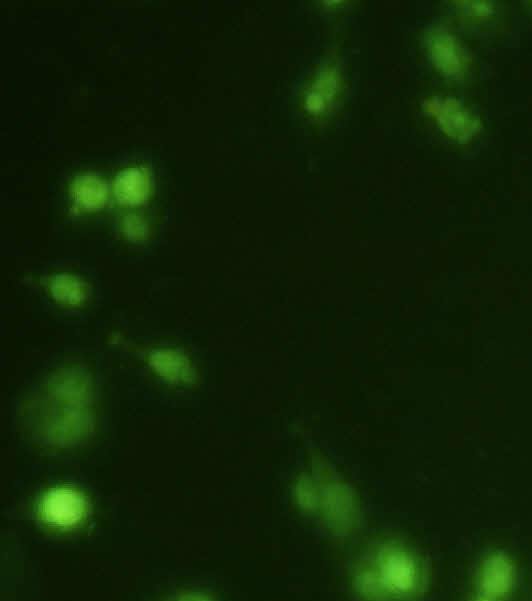

Hoescht staining

The U-87 MG Cells were treated by GCB loaded with MPEG-PCL nanoformulation (GCBNP 3) which shows maximum intracellular accumulation. The cellular uptake of GCB loaded MPEG-PCL nanoparticles in U-87 MG cells were examined under fluorescence microscopy and the images are shown in fig.11.

The results showed significant apoptotic cell death in GCB loaded MPPEGPCL nanoformulation compared with the pure drug. This indicates that the nanoformulation penetrates the cell membrane of glial cells.

Fig. 11: Comparison of penetration of control, pure drug, PNP and GCBNP 3 in U-87 MG cell lines using Hoechst 33342 DNA staining technique